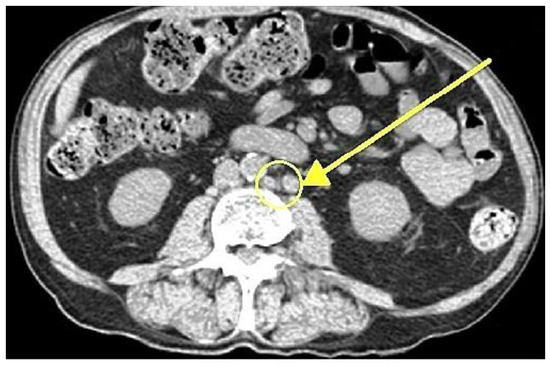

2.2. Detection of Disease Progression

2.3. Preoperative Evaluation and Targeting